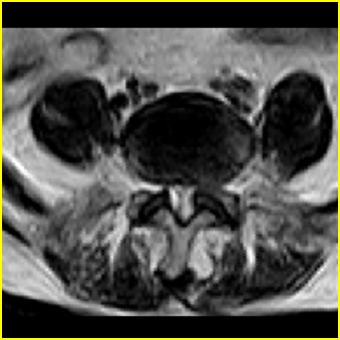

标题: MRI0859:[原创]腰椎,男,78岁,右下肢跛行两月 [打印本页]

男,78岁,右下肢跛行两月.

右侧黄韧带肥厚或钙化,压迫马尾神经所致。必要时行ct扫描。

我认为这一层面椎间盘应该合并左外侧型突出。